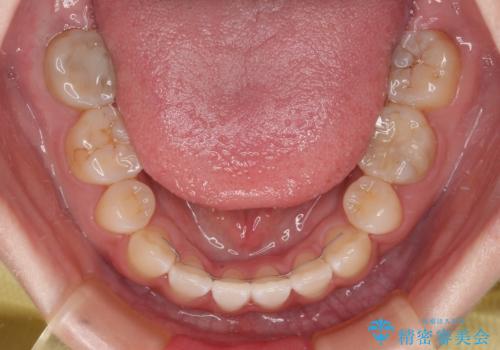

- 口元の突出感と上下前歯のズレを気にして来院された患者様です。

舌の突出癖により上下の前歯は非接触となっている状態でした。

上下左右の第一小臼歯4本を抜歯し、ワイヤー装置にて矯正治療を行うこととしました。